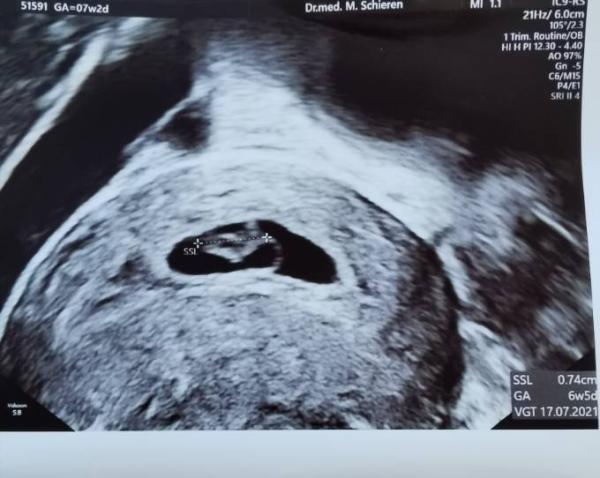

Huhu, Hier mein Update zum Termin gestern. Von 7+2 vorläufig erstmal auf 6+5 zurück. Aber Herzchen schlägt Und soweit schaut alles gut aus. Am 7. Darf ich wieder hin, soll alle 2 Wochen kommen

Bild zu Update 2. Termin FÄ - Forum für Juli - Mamis

Da sieht man ja schon schön was! Herzlichen Glückwunsch!

Wie schön solch eine Entwicklung zu sehen herzlichen Glückwunsch, sieht schon so groß aus